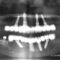

インプラントシュミレーションどおりインプラントを埋入しました。

左右の臼歯部分に3本ずつインプラントを埋入したためインプラントが骨と結合し白い歯が入ればしっかりと奥歯で噛めるようになり不自由なく食事もできます。

今までとにかく忙しくて歯の治療を放置していたとのことでしたので今回しっかりインプラント治療を行えば長期的に噛みあわせが安定し審美性だけでなく食事や発音等もよくなり再度の治療の必要性が大幅に少なくなります。インプラントを埋入した後は骨との結合まで3ヶ月間待たなくてはなりませんがその後はチタン製のアバットメント(白い歯をかぶせるための柱となる部品)を装着し白い歯をかぶせれば治療終了となります。